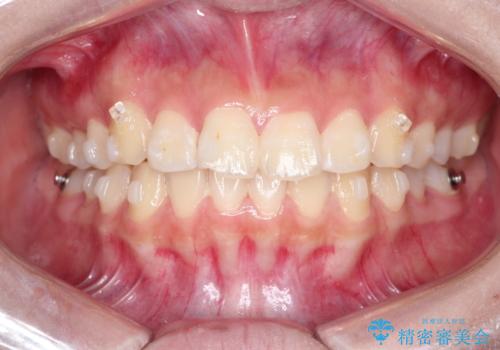

インビザラインによる出っ歯の非抜歯矯正

- インビザラン

- 1年2ヶ月

- 前歯が出ているのを主訴に来院されました。

上の前歯が前方に傾斜しており、上の前歯と下の前歯が接触していない状態でした。

上の奥歯を後方に移動させて、前歯を引っ込める計画としました。

しっかり使っていただけたので、スムーズに治療を終了することができました。